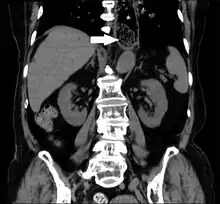

Often it occurs from eating meat and adults and from copins in children.[3][6] The most common risks are eosinophilic esophagitis, Schatzki ring, or esophageal stricture.[3] Other causes include esophageal cancer, reflux esophagitis, and esophageal motility disorders.[3] Diagnosis is generally based on symptoms.[4] CT scan may be useful to detect certain complications.[5]